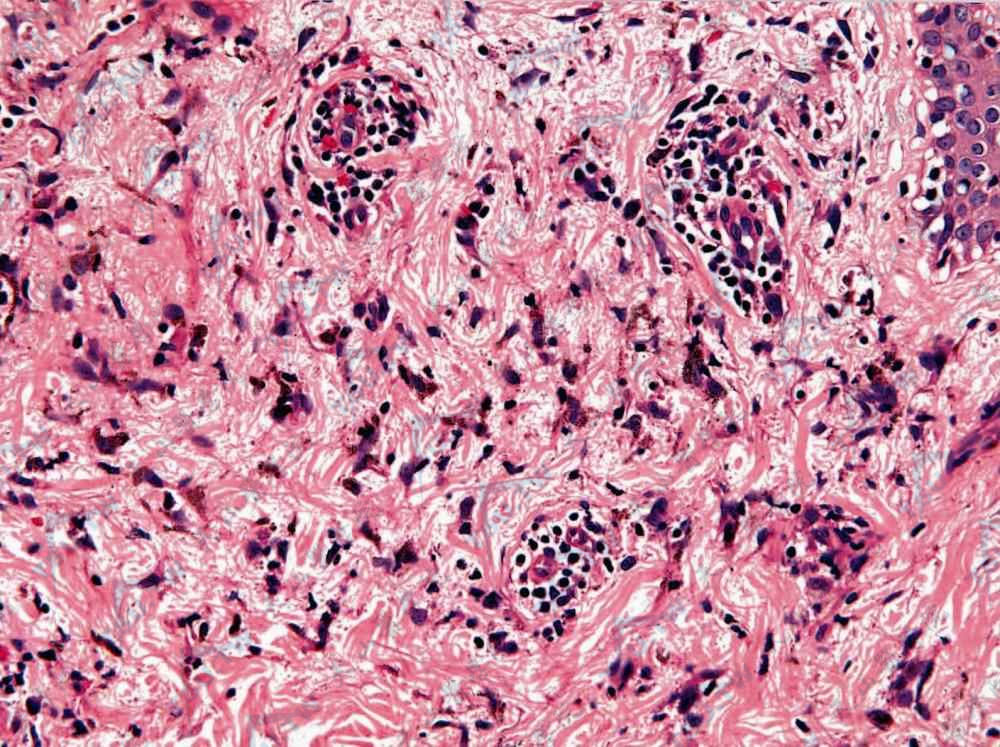

白色萎缩 真皮内小血管壁透明变性,周围炎细胞浸润

图片尺寸1000x663